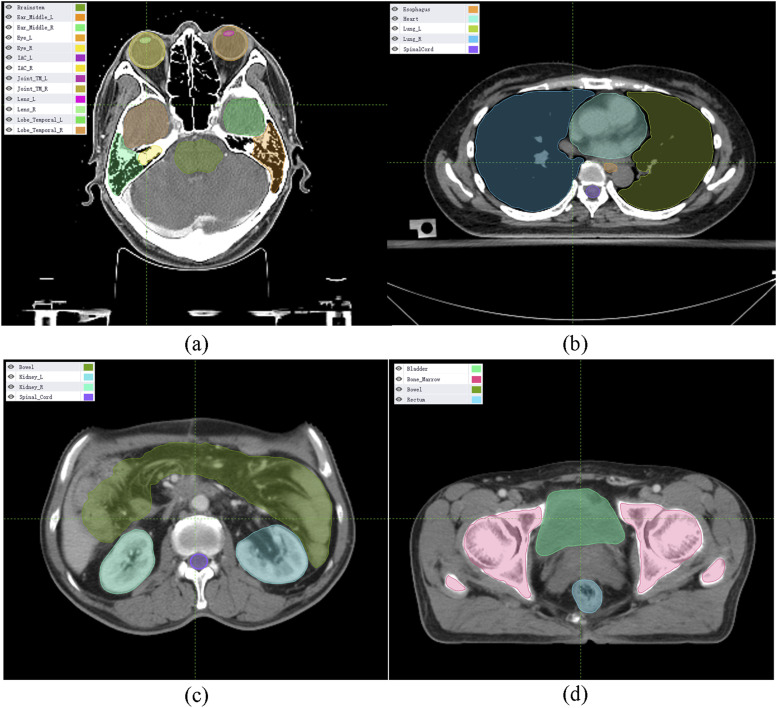

背景和目的:人工智能(AI)是一种试图像人类一样思考并模仿人类行为的技术。由于人类的参与是放射治疗(RT)中主要的不确定性来源,因此人工智能被认为是放射治疗(RT)中许多依赖人类的步骤的替代方案。这项工作的目的是对目前有关人工智能在放射治疗中应用的文献进行系统总结,并从临床角度阐明人工智能在放射治疗实践中的作用:对 PubMed 和 Google Scholar 进行了系统的文献检索,以确定从开始到 2022 年涉及 RT 中人工智能应用的原始文章。如果研究报告了原始数据并探讨了人工智能在 RT 中的临床应用,则被纳入研究:所选研究分为 RT 的三个方面:器官和病灶分割、治疗计划和质量保证。针对每个方面,本综述讨论了这些人工智能工具如何参与到 RT 方案中:我们的研究表明,在复杂的 RT 过程中,人工智能是依赖人力的步骤的潜在替代方案。

Results: The selected studies were categorized into three aspects of RT: organ and lesion segmentation, treatment planning and quality assurance. For each aspect, this review discussed how these AI tools could be involved in the RT protocol.